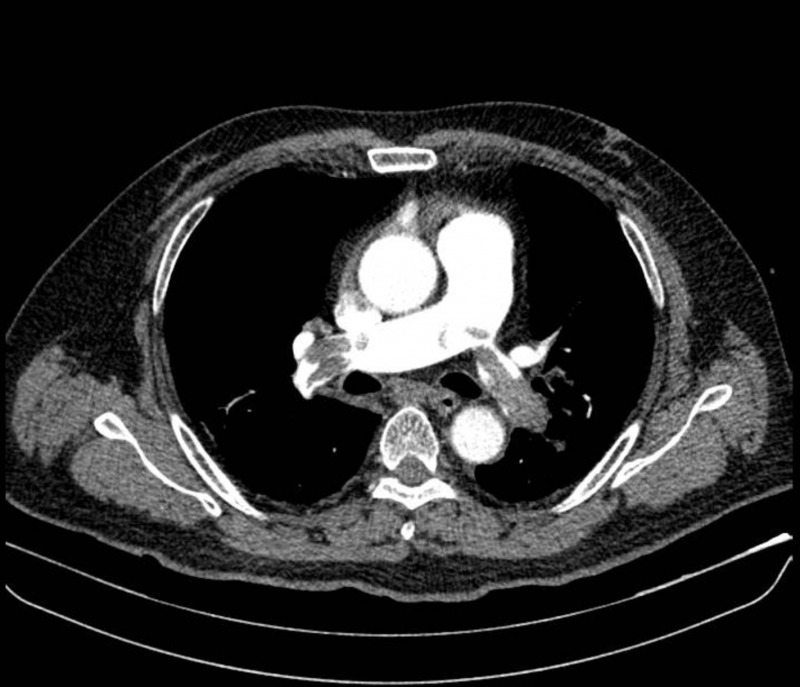

Tại tuyến đầu, ông được chẩn đoán nghi nhồi máu cơ tim và nhanh chóng chuyển viện. Kết quả chụp CT mạch máu phổi tại Bệnh viện Nhân dân 115 cho thấy ông bị thuyên tắc phổi cấp, huyết khối lớn bít tắc hai bên động mạch phổi, gây sốc tắc nghẽn. Bệnh nhân được điều trị bằng thuốc tiêu sợi huyết, hồi phục sau một tuần.